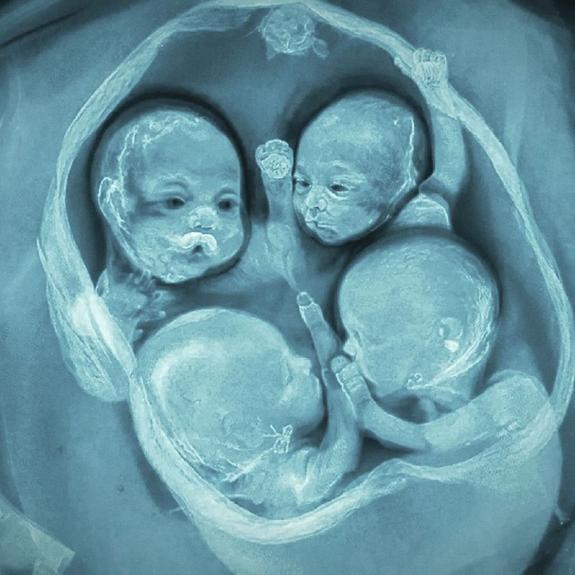

В одном из роддомов Санкт-Петербурга зафиксирован уникальный случай: женщина родила однояйцевых четверняшек — четырех девочек. Это первые такие роды в России.

Дети появились на свет на 32-й неделе беременности с помощью кесарева сечения. Заместитель главврача уточнил, что для многоплодной беременности этот срок является нормой.

Состояние малышек оценивается как хорошее, за ними наблюдают неонатологи. Вес новорожденных составляет от 1360 до 1640 граммов, рост — от 37 до 41 сантиметра.

Всего в мире насчитывается около 15 случаев рождения идентичных четверняшек, из них 10 — девочки. Частота такого явления — примерно один случай на 15,5 миллионов родов.